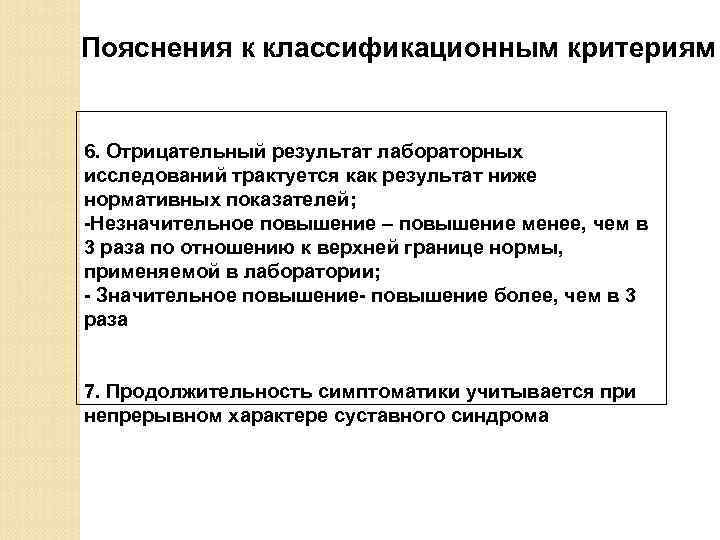

Пояснения к классификационным критериям 6. Отрицательный результат лабораторных исследований трактуется как результат ниже нормативных показателей; -Незначительное повышение – повышение менее, чем в 3 раза по отношению к верхней границе нормы, применяемой в лаборатории; - Значительное повышение- повышение более, чем в 3 раза 7. Продолжительность симптоматики учитывается при непрерывном характере суставного синдрома

Пояснения к классификационным критериям 6. Отрицательный результат лабораторных исследований трактуется как результат ниже нормативных показателей; -Незначительное повышение – повышение менее, чем в 3 раза по отношению к верхней границе нормы, применяемой в лаборатории; - Значительное повышение- повышение более, чем в 3 раза 7. Продолжительность симптоматики учитывается при непрерывном характере суставного синдрома